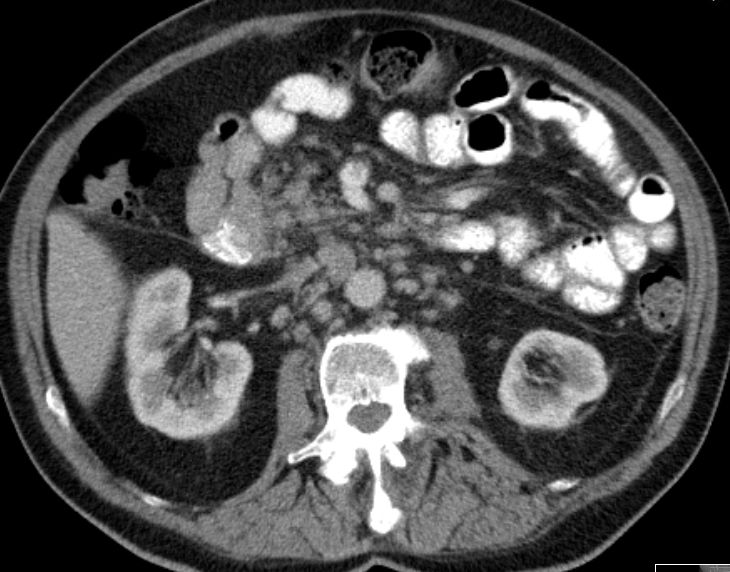

| Metastasen | zahlreiche vergrößerte Lymphknoten paraaortal, paracaval und mesenterial.![]() |

| Ileus | 78-jährige Frau in der Notaufnahme wegen Ileus. Tumor am deszendo-sigmoidalen Übergang. Hemokolektomie: Ulzeriertes Adenokarzinom pT3b pN1a (1/12)Mo L1 Vo. | ||

| Ileus | Das CT zeigt einen stenosierenden Sigmatumor mit ausgeprägtem Ileus. |